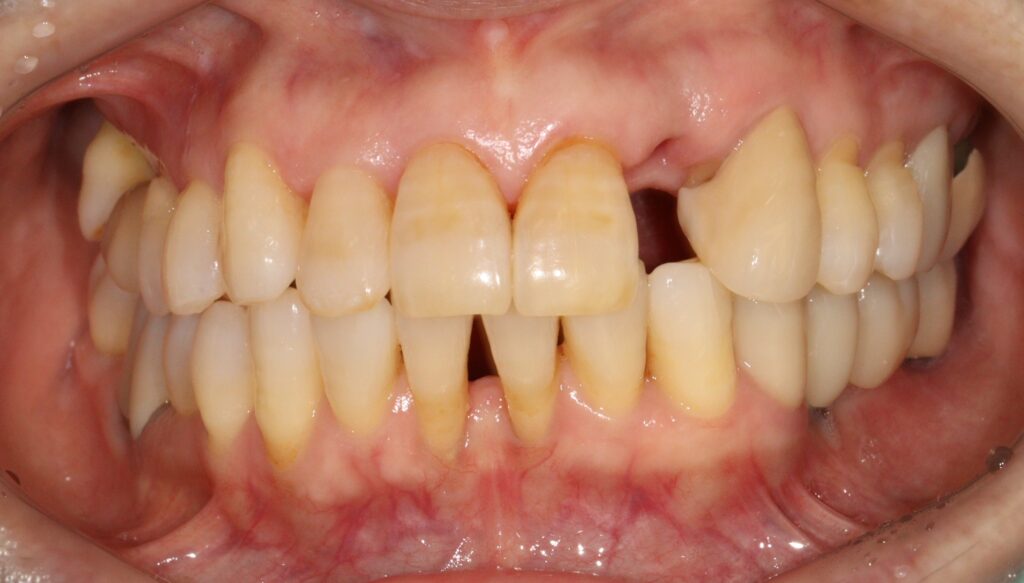

아래 앞니는 잇몸쪽으로 보이는

블랙트라이앵글과 잇몸 퇴축이 심하고

치아의 뿌리 형태를 다 채울 수는 없어서

뿌리쪽보다는 머리 부분의 공간만 채우는

디자인으로 해서 잇몸에 자극되지 않도록

치료를 마무리 하였습니다.